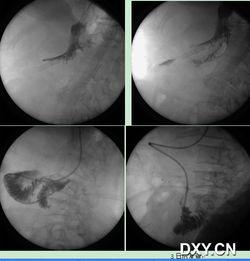

5. 确认位置:医生通过X光片确认鼻肠管已经到达小肠,确保操作成功。